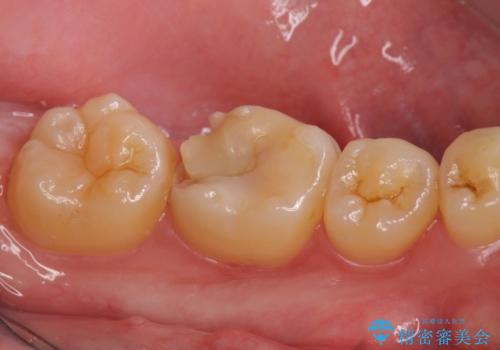

- 左下6の歯が欠けてしまったので診て欲しいといらっしゃった方の症例です。

虫歯除去後、オールセラミッククラウンによる補綴を行いました。